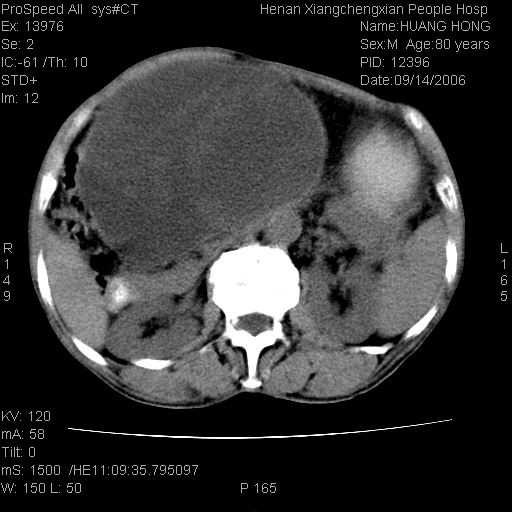

患者, 男, 80岁, 发现上腹部包块1年余,无其它不适.2006-9-14ct片是喝水后扫描2006-9-15ct片没喝水扫描![]() ![]() ![]() ![]() ![]() ![]() ![]() ![]() ![]() ![]() ![]() ![]() ![]() ![]() ![]() ![]() 以上是喝水片 以下是空腹片 ![]() ![]() ![]() ![]() ![]() ![]() ![]() ![]() ![]() ![]() ![]() ![]() ct:胰腺前方、肝脏与胃之间可见巨大类圆形囊性低密度影,大小约152mmx145mmx118mm,上缘平t11椎体上缘,下缘平l3椎体下缘,密度均匀,ct值15hu,其内呈多房分隔,囊壁薄且光滑,边界清晰,周围组织及器官明显受压。肝脏实质内未见异常密度影,胆囊未见异常,胰腺密度未见异常,脾脏大小、形态及密度未见异常,腹膜后间隙未见肿大淋巴结影。 印象:胰腺前方、肝脏与胃之间巨大类圆形囊性低密度影.性质待定。多考虑:.肠系膜巨大囊肿。 守望可可西里发言:支持楼主,考虑肠系膜囊肿,多为小肠系膜。 ysxyy发言:我总觉得这个病人虽然很像肠系膜囊肿,但还是应该强化一下; 下面这几幅图里肿块和主动脉的关系不太清,不知能否除外血管性来源? ![]() ![]() ![]() 病理结果:横结肠系膜间叶瘤.部分区域间质细胞增生活跃. 病理图片 ![]() 良性间叶瘤:是指由两种或两种以上的间叶组织所构成的混合性肿瘤.肿瘤仅发生在腹膜后和肠系膜,.前者较后者多发.良性间叶瘤常发生在肾或四肢,腹膜后较少见,各年龄均可发病.女多与男,预后较好,但术后易复法. 恶性间叶瘤:由两种以上恶性间叶组织成分组成. 光镜:肿瘤由脂肪/血管/平滑肌构成. 原贴地址: http://www.radinet.com.cn/forum_view.asp?forum_id=4&view_id=16217 ok |